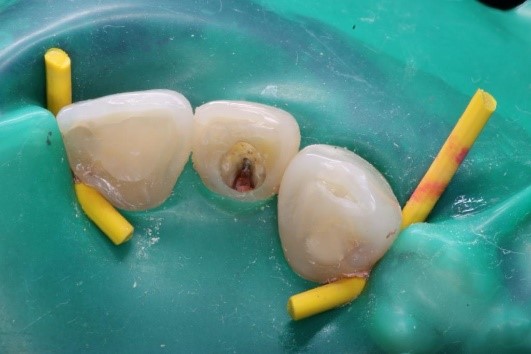

La figura 3 se muestra la apertura de la cámara pulpar y se retira todos los restos de la obturación.

Figura 3. Apertura de la cavidad